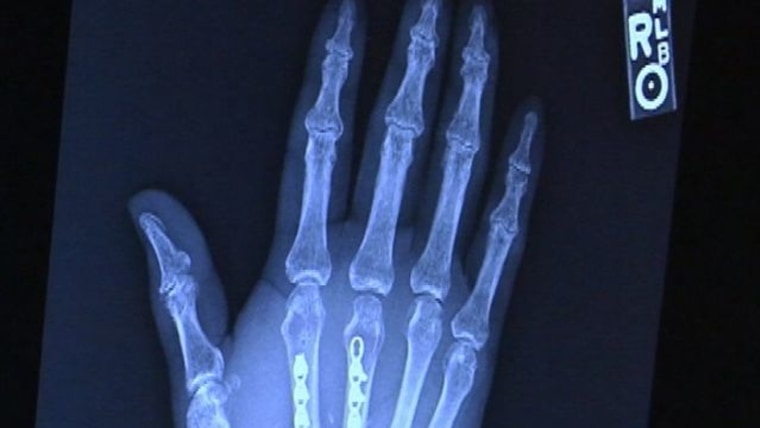

'Nerve harvest' helps rebuild man's hand

Doctors use bones, nerves and other tissues from man's own body to rebuild his hand. KPLC's Britney Glaser reports.